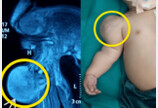

출생 직후 어깨 혹 있던 신생아…6.5cm 희귀 섬유육종 판정생후 한 달 아기의 팔에서 점점 커진 혹이 저등급 영아 섬유육종으로 진단됐다. 수술로 종양을 제거한 뒤 1년간 재발 없이 정상 성장 중이다.2025-08-26 10:50:35